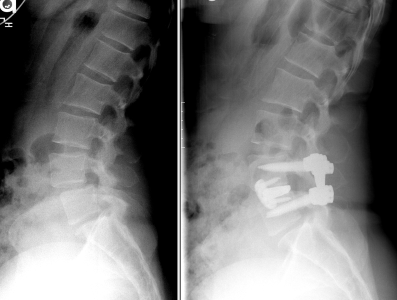

Dr. Farokhi with patientHer journey to healing began when she met Dr. Frank Farokhi, a neurosurgeon at Ascension Sacred Heart Neurosurgery in Pensacola, who specializes in advanced spinal procedures. After evaluating her condition, Dr. Farokhi recommended an Oblique Lumbar Interbody Fusion (OLIF) , a minimally invasive, lateral spinal fusion technique designed to relieve pressure on the nerves, stabilize the spine, and restore mobility.

“Myself and my colleague are the only surgeons in the region offering this specialized procedure. I use OLIF to access the spine from the side of the body with less disruption to muscles and tissues,” explained Dr. Farokhi. “This means less pain, fewer complications, and a faster recovery for patients as our goal is always to treat not just the condition, but the whole person.”

spine xray pre and post surgery.After surgery, Stephanie’s pain was gone. “I have my life back,” she said. “Dr. Farokhi told me I would walk with a straight spine again and that gave me hope. His skill and genuine care made all the difference in my recovery.”